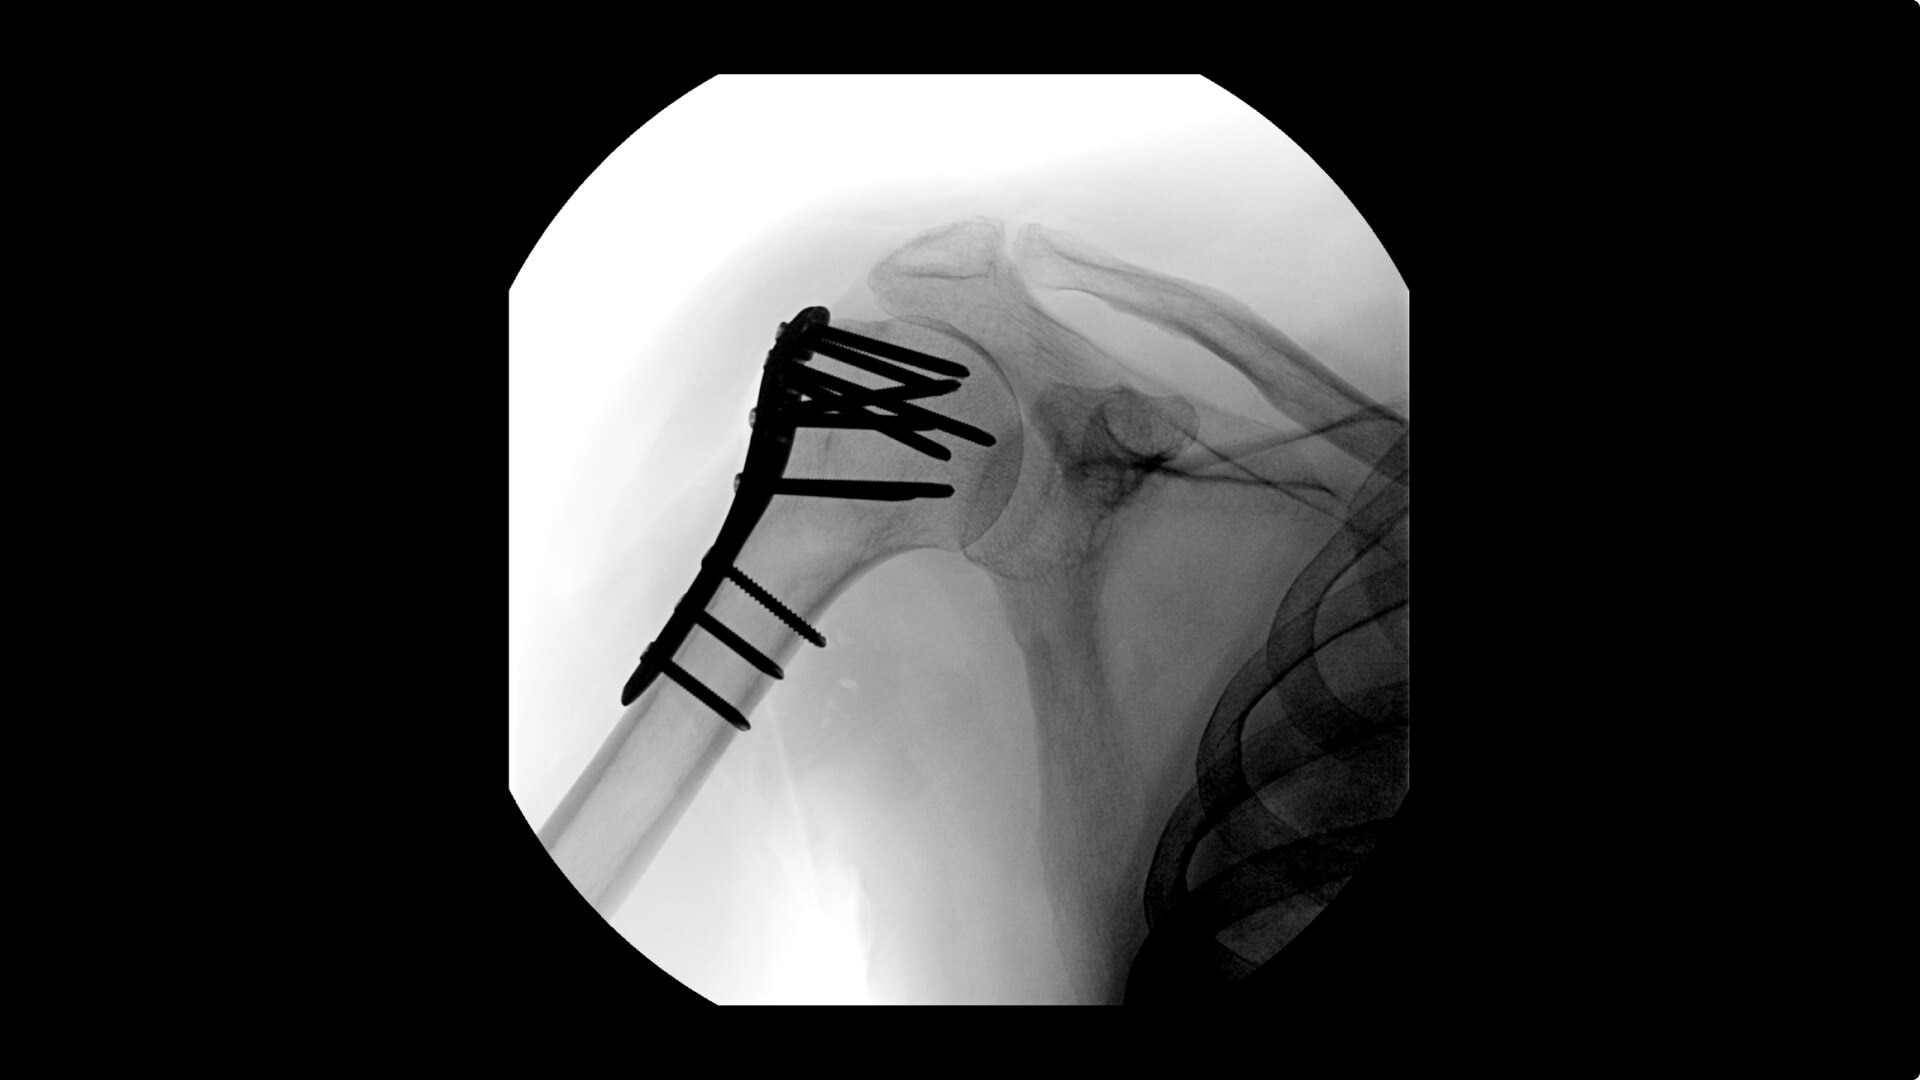

• Humeral fracture

• Shoulder fracture reduction

Complex orthopedic procedures require powerful imaging systems. OEC premium C-arms perform in a variety of procedures such as:

OEC C-arms provide orthopedic imaging with a large field of view optimized to clearly visualize orthopedic anatomy, such as the entire long bone femur or minute fractures in extremities. A clear display with comfortable viewing can easily show AP and lateral views, enabling efficient procedure planning.